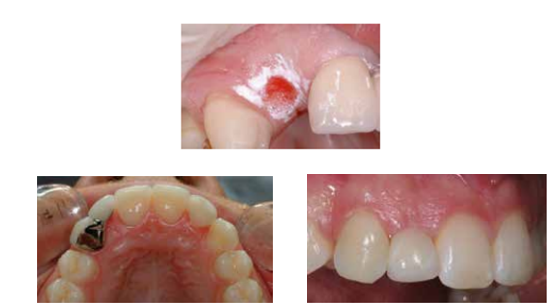

What is an ovate pontic?

A pontic design requiring soft tissue surgery, mostly used for anterior teeth.